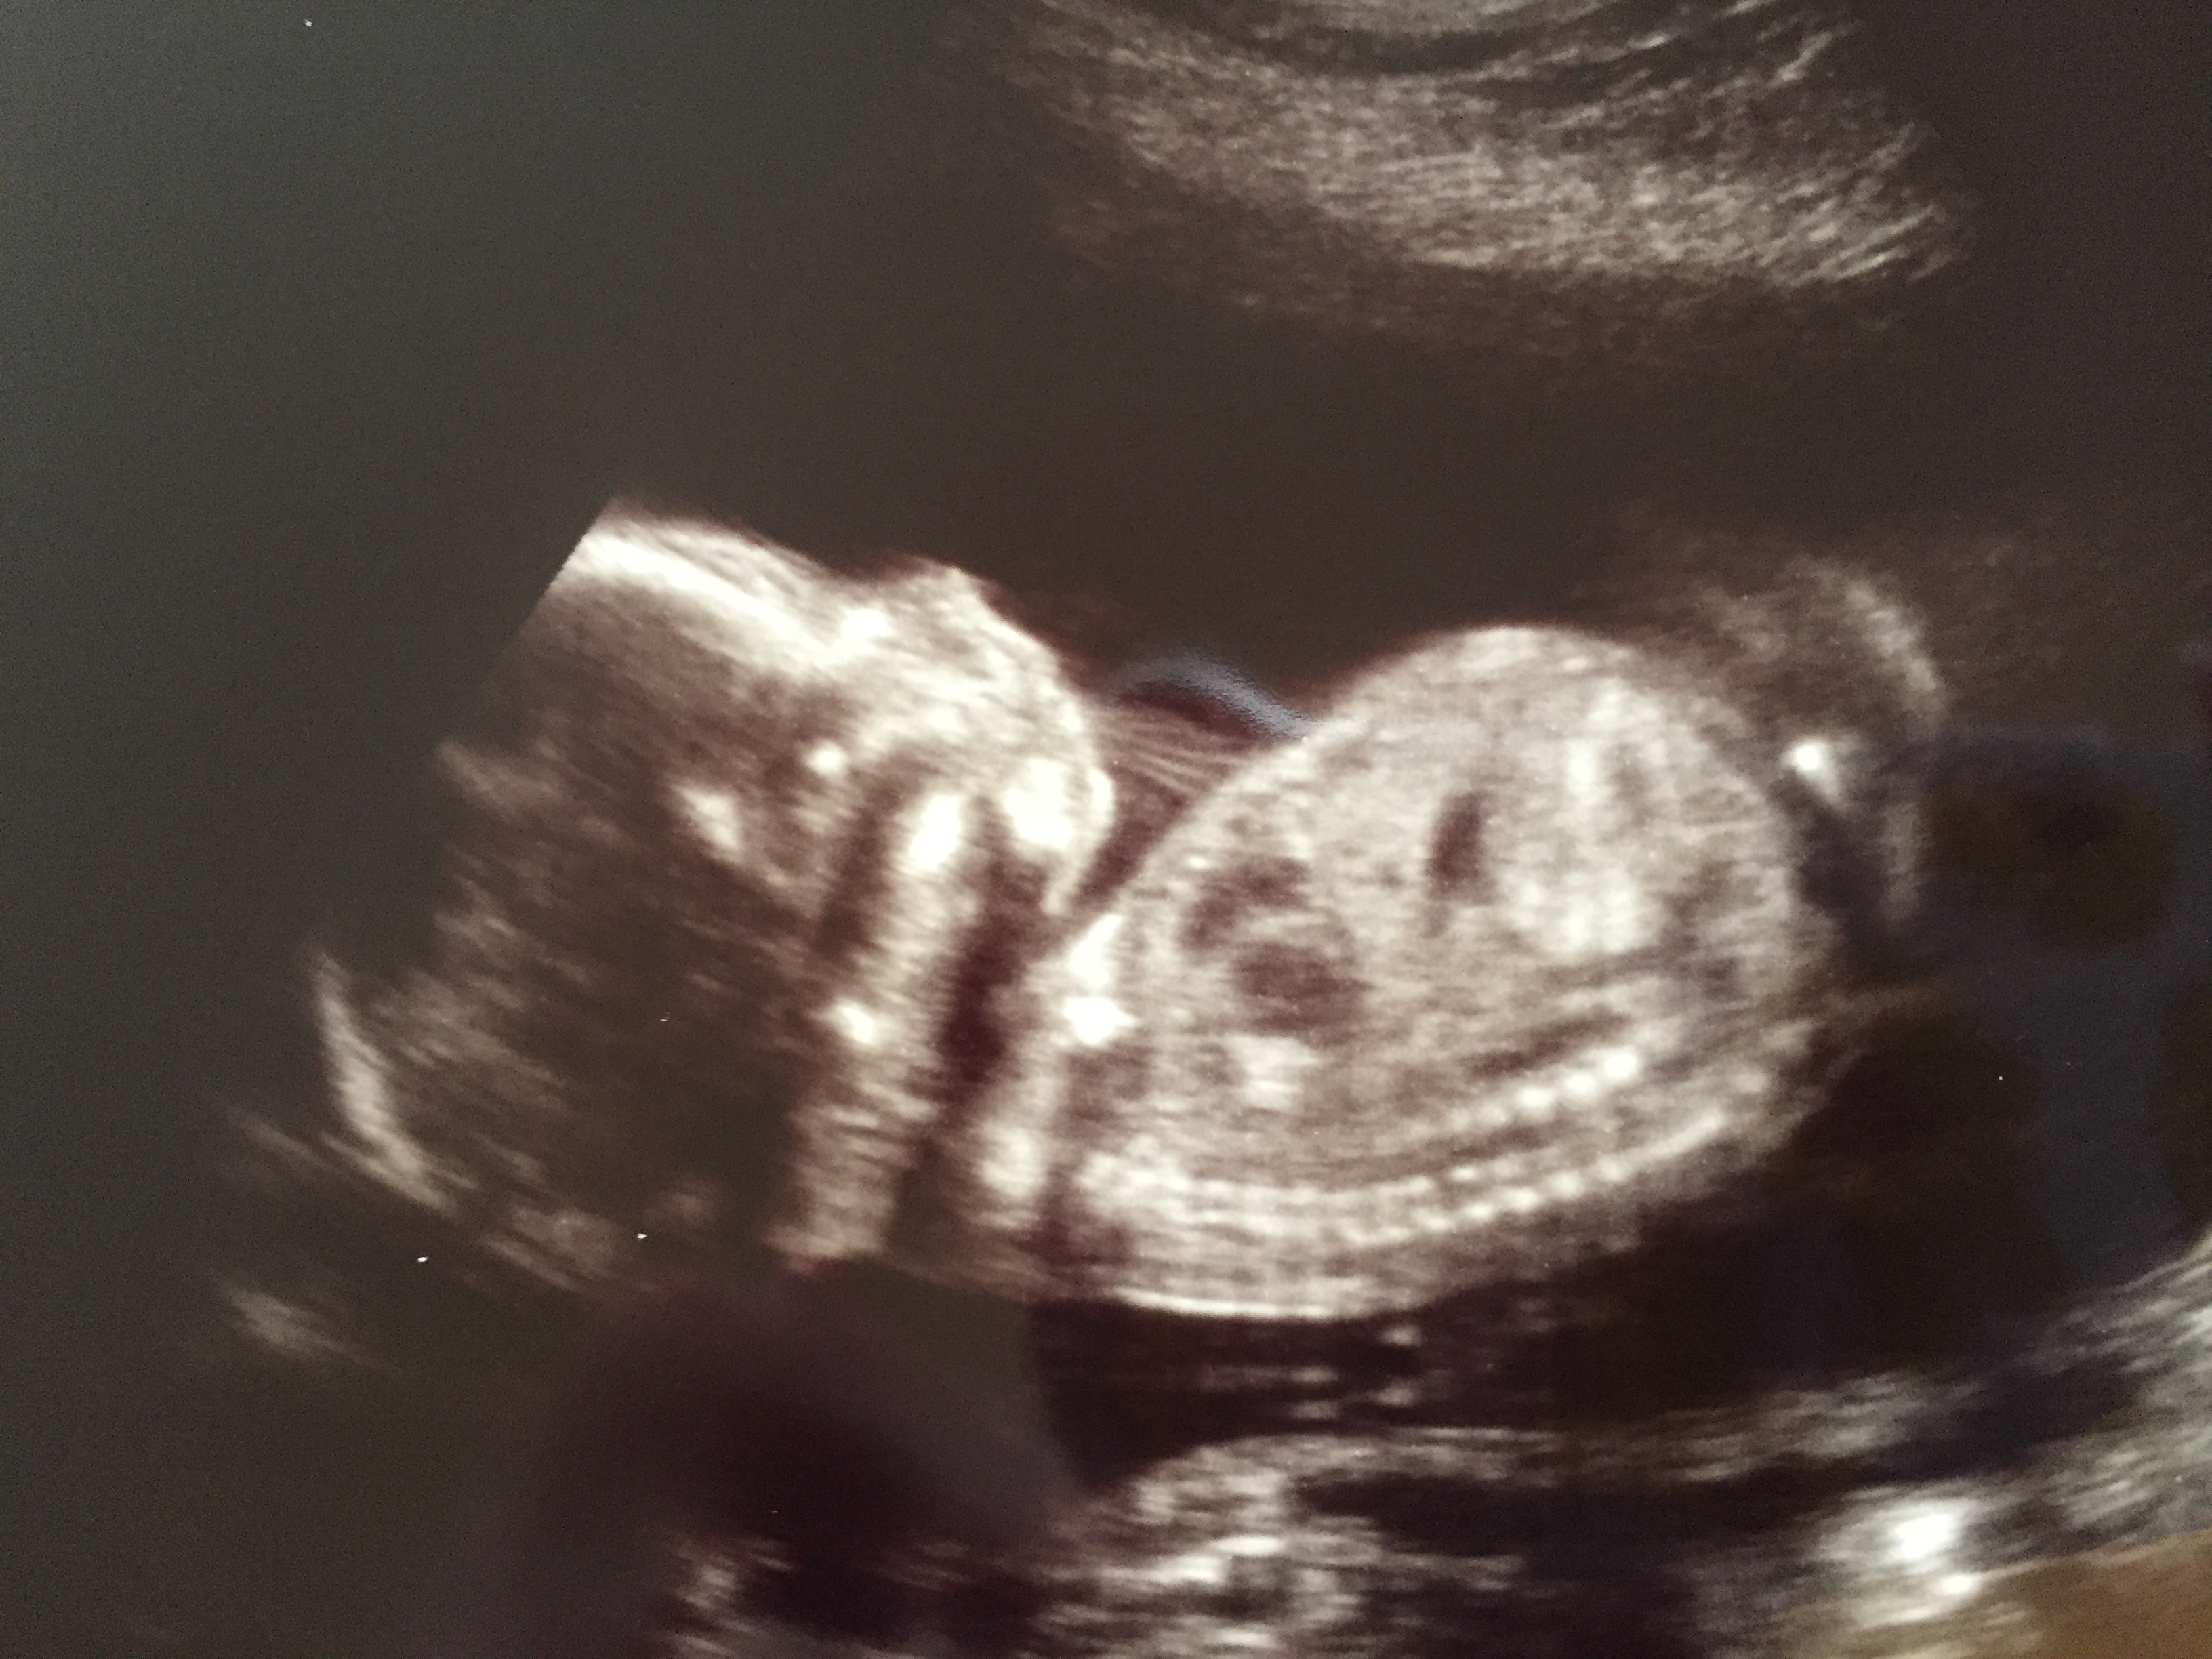

Baby ProfileWhen I first announced that Andrew and I were expecting our first child, I was bombarded with horror stories about pregnancy and childbirth.  All of a sudden, everyone seemed to know someone who’d had an awful experience carrying and/or giving birth to their child.  And they all felt a strong desire to share these stories with me.  As you can imagine, it was exactly what a twenty-six year old woman, pregnant for the first time, wanted to hear.

IMG_0567And then there were a few things that took me by surprise, but in the best way possible.  I had been ready for many of the perks of pregnancy, but there have been several realizations that I was totally unprepared for.  Some of them have been unique to me, but others are probably experienced by many pregnant women, but don’t get the same spotlight as cravings (when your husband is willing to stop at Wawa on your way home from church because you have a sudden need for soft pretzels) or maternity clothing (when you realize what the rest of the world is missing when you try on your first pair of maternity jeans).  Even if these perks don’t get their own pages on thebump.com or fitpregnancy.com, they are definitely worth knowing about.